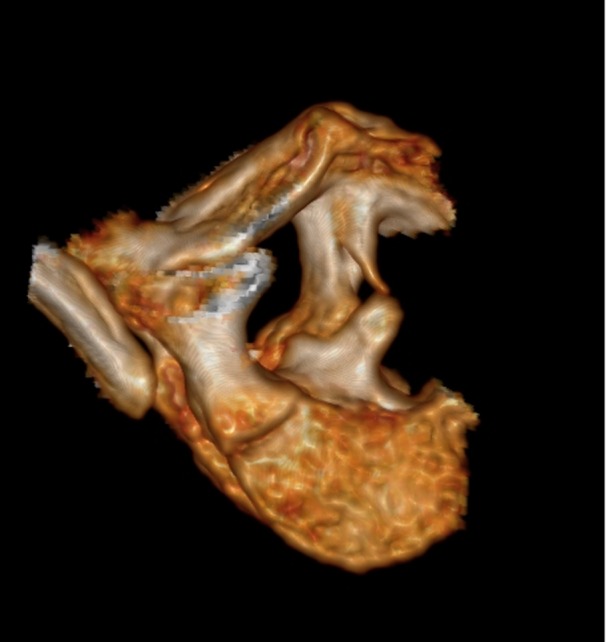

The skin of all the subjects had signs at the region of the back, similar to local hypertrichosis, hemangiomas, or skin dimpling (a representative image is shown in Fig. 2). Widening of the interpedicular distance at the level of one or a few vertebral segments is a very distinctive feature for patients with diastematomyelia as shown in Fig. 3. In such cases, the presence of spinal cord splitting was clearly visualized on MRI (Fig. 4). CT images provided the necessary information to differentiate between bony and fibrotic septum (Fig. 5). In our population, 18 (90%) subjects had different types of congenital vertebral anomalies, including failure of formation, segmentation and a combination of aforementioned, while 17 (85%) subjects had congenital scoliosis. In 2 (10%) subjects with fibrotic septum, there were no congenital abnormalities. The most commonly seen musculoskeletal deformity in subjects with diastematomyelia was lower limb asymmetry. Atrophy with increasing muscle weakness was thought to be a case of neurological deterioration, thus being an indication for surgery. Partial restorations of neurological function were observed in total four subjects, for whom spur resection surgery was carried out.

Fig. 5.

3D reconstruction of the CT showing two bony spuns in the vertebral canal. Diastemas of such extension are quite rare